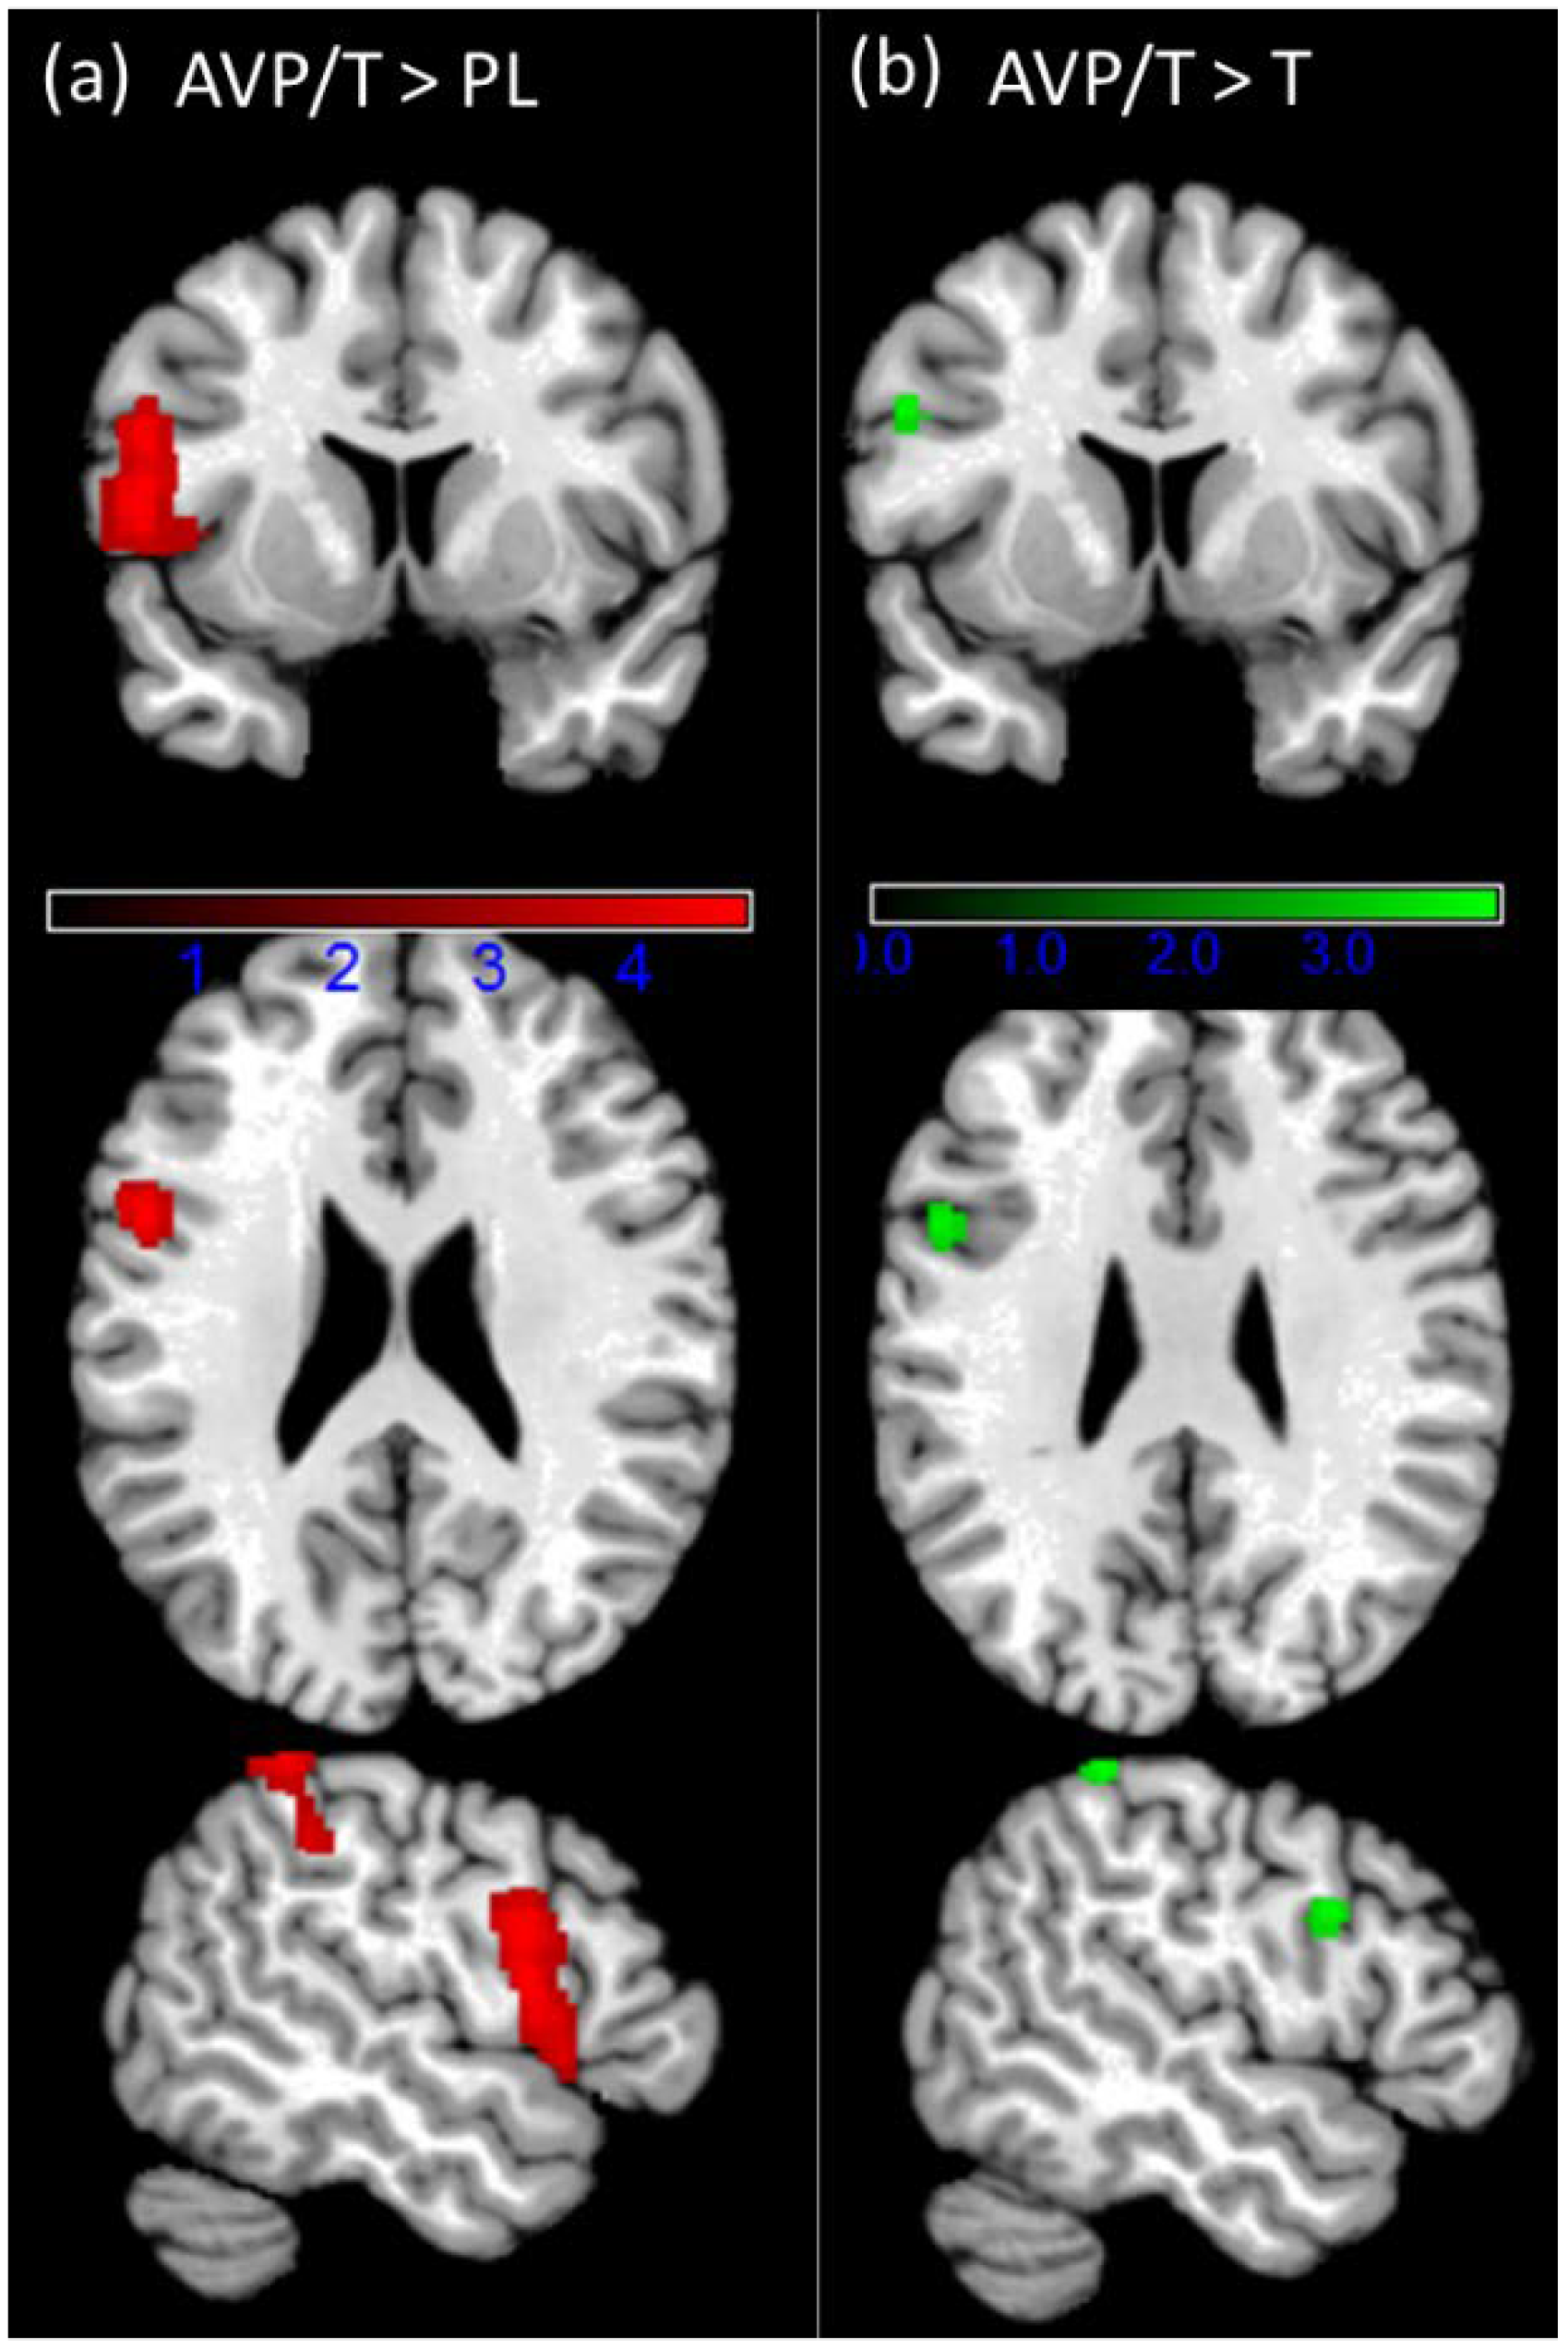

| Contrast | Region | k | T | x | y | z |

|---|---|---|---|---|---|---|

| L Insula Lobe | 12,210 | 8.29 | −40 | 0 | 8 | |

| R Caudate Nucleus | 8.15 | 8 | 12 | −12 | ||

| L Putamen | 8.13 | −14 | 12 | −10 | ||

| L Insula Lobe | 7.83 | −38 | 4 | 2 | ||

| L IFG (p. Opercularis) | 7.74 | −52 | 4 | 6 | ||

| R Caudate Nucleus | 7.63 | 16 | 12 | −12 | ||

| Win > loss | L Middle Temporal Gyrus | 7.62 | −44 | −64 | 10 | |

| R Putamen | 7.42 | 22 | 10 | 2 | ||

| R Middle Temporal Gyrus | 869 | 8.84 | 42 | −72 | 8 | |

| R Cuneus | 424 | 6.89 | 18 | −78 | 40 | |

| R Superior Occipital Gyrus | 6.37 | 20 | −90 | 34 | ||

| R Cuneus | 5.66 | 14 | −92 | 22 | ||

| R SupraMarginal Gyrus | 382 | 6.84 | 58 | −38 | 24 | |

| R Superior Temporal Gyrus | 6.73 | 62 | −36 | 16 | ||

| L SupraMarginal Gyrus | 376 | 6.54 | −60 | −26 | 34 | |

| L Lingual Gyrus | 2632 | 9.34 | −24 | −98 | −14 | |

| L Inferior Occipital Gyrus | 9.19 | −36 | −90 | −12 | ||

| L Fusiform Gyrus | 8.70 | −42 | −82 | −14 | ||

| L Middle Occipital Gyrus | 7.25 | −32 | −96 | 0 | ||

| R Lingual Gyrus | 2117 | 8.21 | 20 | −96 | −12 | |

| R Calcarine Gyrus | 8.20 | 18 | −102 | −6 | ||

| R Inferior Occipital Gyrus | 8.11 | 38 | −88 | −14 | ||

| R Middle Temporal Gyrus | 3.92 | 64 | −40 | −12 | ||

| R IFG (p. Orbitalis) | 1058 | 5.15 | 48 | 26 | −14 | |

| Loss > win | R Inferior Temporal Gyrus | 4.67 | 48 | 6 | −36 | |

| R Medial Temporal Pole | 4.05 | 44 | 12 | −28 | ||

| R Middle Temporal Gyrus | 4.02 | 54 | −26 | −12 | ||

| R IFG (p. Orbitalis) | 4.01 | 40 | 38 | −18 | ||

| R Medial Temporal Pole | 3.97 | 52 | 6 | −24 | ||

| R Superior Medial Gyrus | 849 | 4.92 | 10 | 28 | 62 | |

| L Superior Medial Gyrus | 4.26 | −6 | 52 | 22 | ||

| R Superior Parietal Lobule | 508 | 6.02 | 36 | −76 | 50 | |

| R Angular Gyrus | 4.54 | 50 | −64 | 24 | ||

| L Inferior Parietal Lobule | 488 | 4.93 | −36 | −68 | 48 | |

| L Angular Gyrus | 3.95 | −52 | −56 | 28 | ||

| L Middle Temporal Gyrus | 4.68 | −58 | −24 | −16 | ||

| L Precuneus | 371 | 5.78 | 0 | −68 | 36 | |

| R MCC | 3.62 | 8 | −52 | 34 | ||

| L IFG (p. Orbitalis) | 371 | 5.57 | −30 | 22 | −24 | |

| L Temporal Pole | 5.02 | −42 | 20 | −24 |